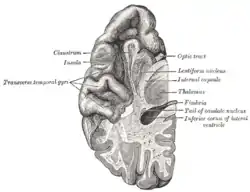

Section of brain showing upper surface of temporal lobe ("transverse temporal gyri" visible at center left) | |